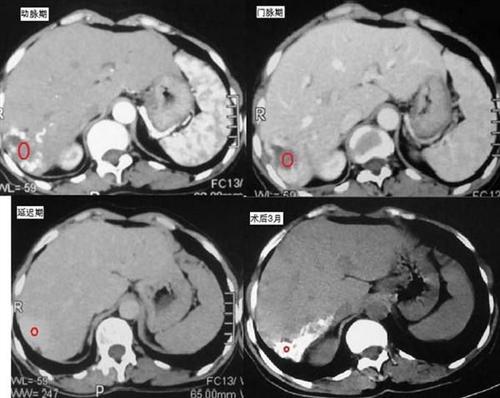

肝包膜下大血肿破裂出血样子像肿瘤而非肿瘤 - 好大夫在线

肝尾叶巨大混杂密度包块一例 [病例帖]